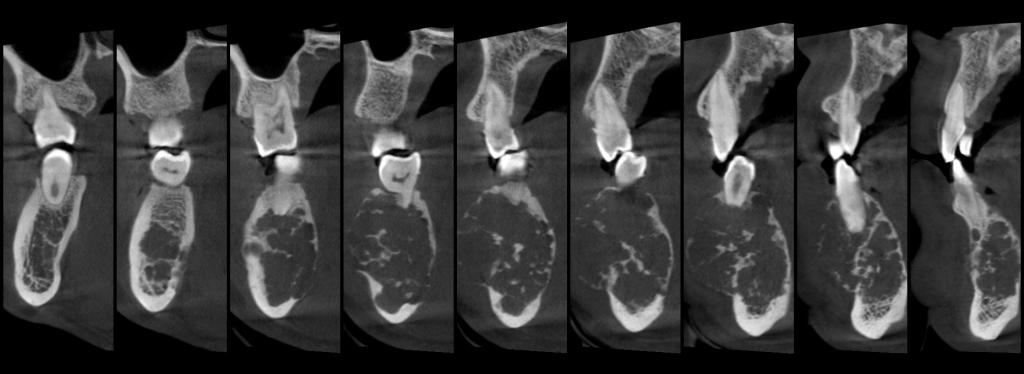

颅颌面CBCT

诊断范围涉及牙体牙髓病、牙周病、阻生牙/多生牙定位、种植牙术前CT评估分析、颞下颌关节CT诊断分析、,颌骨及涎腺疾病、颌面发育畸形、正畸治疗辅助诊断等大部分颌面部疾病,为临床医疗提供强有力的支持。